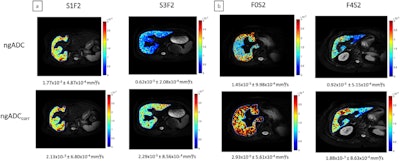

Representative parametric maps of ngADC (at the top) and ngADCcorr (at the bottom); (a) The effect of steatosis is depicted in two patients with identical F2 fibrosis stage but varying steatosis grade; (b) The effect of fibrosis is depicted in two patients with identical steatosis grade (S2) but varying fibrosis stage. In the uncorrected coefficient map, differences of ngADC are seen for steatosis (1.77 × 10-3 vs. 0.62 × 10-3 mm2/s), while in the corrected coefficient map, differences of ngADCcorr are seen for fibrosis (2.93 × 10-3 vs. 1.88 × 10-3 mm2/s). Images and caption courtesy of the JMRI.